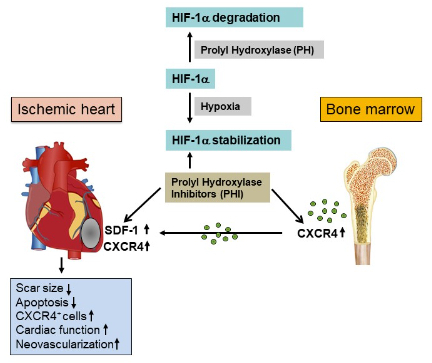

Our major research goal is the development of novel therapies based on inflammatory, chemokine-driven and aging-related mechanisms to treat ischaemic and non-ischaemic cardiomyopathies. Using genetic mouse models, we specifically investigate the impact of smooth muscle-specific knockout of the chemokine SDF-1 on cardiovascular development and regeneration. Moreover, we are interested in stimulating cardiac repair mechanisms based on the activation of HIF-1 target genes by prolyl hydroxylase inhibitors and in analysing aging-related splicing variants in patients with cardiomyopathy.

- Cell-specific role of SDF-1 in the recruitment of progenitor cells after myocardial ischaemia

Ongoing research suggests a fundamental role of the SDF-1/CXCR4 axis in cardiac repair and tissue homeostasis after ischaemia. Nevertheless, there is still little understanding of the precise cellular mechanisms by which SDF-1-dependent cell migration is orchestrated. In our current FWF-funded project, we aim to identify important cellular sources of SDF-1-dependent cell recruitment and cardiac repair. Based on previous work and preliminary data, we aim to investigate the cell-specific effects of SDF-1 ablation in smooth muscle cells within the cardiovascular system, using conditional, SDF-1-specific knockout mouse models. Moreover, we elucidate the therapeutic potential of HIF prolyl hydroxylase inhibitors (PHI) to induce SDF-1 gene expression and stimulate cardiac repair in the ischaemic heart. Our data suggest that the inhibition of prolyl hydroxylase may be a promising target for HIF-1a-mediated SDF-1 activation, to increase stem cell homing and myocardial repair (see Fig. 2).

Under normoxic conditions, HIF-1a protein is inactivated by prolyl hydroxylases, leading to HIF-1a degradation. Hypoxia or PHI leads to reduced prolyl hydroxylase activity, thus stabilising HIF-1a, which translocates to the nucleus and upregulates downstream target genes.